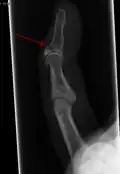

- Radiographie montrant une fracture à l'insertion du tendon extenseur